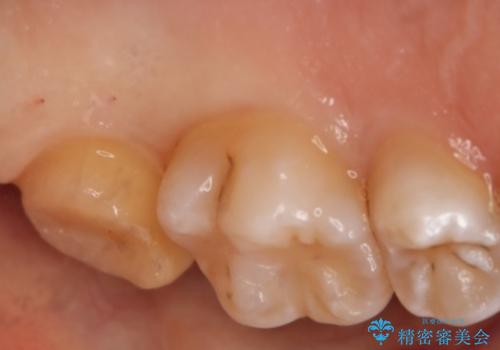

- 左上7番の虫歯治療を主訴に来院された患者様です。

虫歯の範囲が広かったので切削量・形態を考慮し、セラミッククラウンでの治療を計画しました。

虫歯の範囲が広い場合、大きく削る必要があるので部分的に詰めるインレーではなく、クラウンでの治療になることがあります。